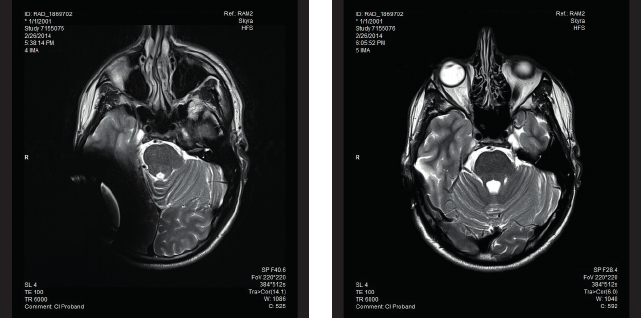

Fig. B Image artefacts arising in a . T scanner. The left picture shows the artefacts obtained with

the implant magnet in place whereas the right picture illustrates the image artefacts when the implant

magnet is replaced with the Non-Magnetic Spacer.

Fig. C Image artefacts arising in a . T scanner. The left picture shows the artefacts obtained with